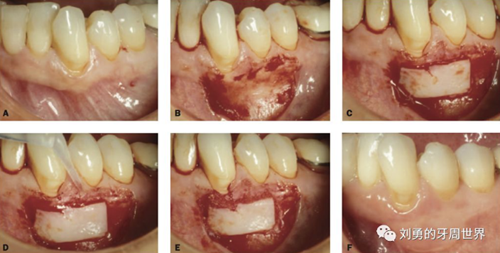

接下來討論一下供區(qū)取瓣的厚度,老外的建議是:

薄或中等厚度最好用于增加附著齦,厚或全厚推薦用于根面覆蓋和牙槽增量手術(shù)。

原因是:附著齦增寬的手術(shù),受區(qū)骨膜面積大,血供好,因此用偏薄的就可以,而對(duì)于根面覆蓋的手術(shù),受區(qū)外露根面沒有骨膜,血供差,因此取厚一點(diǎn)的,容易成活,對(duì)于牙槽嵴缺損的,建議取厚的,不是為了血供,而是為了更明顯的修復(fù)牙槽嵴的缺損。如下圖:

上面是附著齦增寬,因此取的薄一些。

上圖B23頰側(cè)牙槽嵴水平向塌陷明顯,為了增寬,取厚一點(diǎn)的齦瓣效果更好。